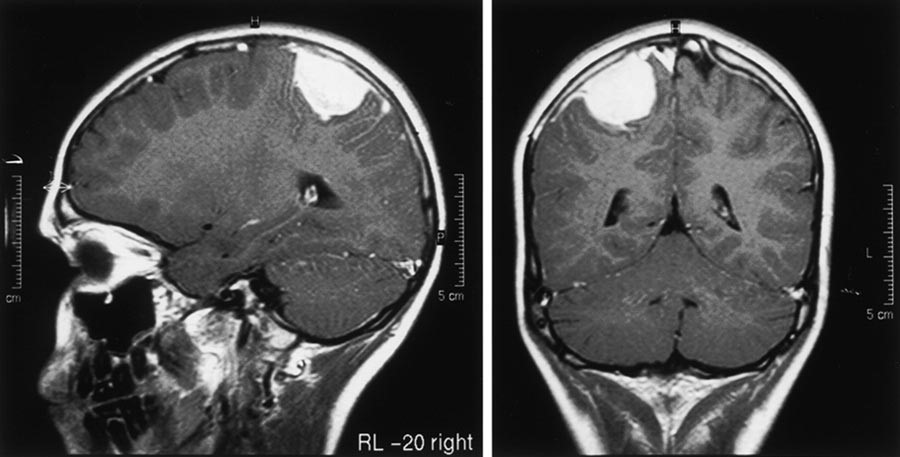

Применение современных методов исследования, таких как МРТ головного мозга, позволяет более точно выявить причины менингеального синдрома. Обращение к специалистам при появлении первых симптомов крайне важно, так как ранняя диагностика способствует более эффективному лечению и снижению риска осложнений.

Важным инструментом для диагностики служат визуализирующие методы, среди которых наибольшее значение имеет МРТ головного мозга. Это исследование позволяет получить подробные изображения мозга и его оболочек, что даёт возможность определить наличие воспалительных процессов, опухолей или других аномалий. Кроме того, необходимо провести анализ ликвора, который может выявить инфекционные агенты и признаки воспаления.